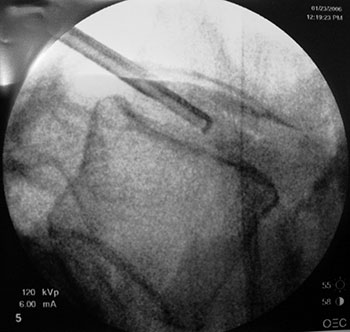

Outro método possível de obter o ponto de entrada do fio guia é utilizando uma imagem oblique em 45o, sendo que o ponto de entrada deve localizar-se logo lateral à faceta (Fig. 4), de modo a penetrar exatamete na zona triangular de segurança.

Fig. 4

Após a introdução do fio guia procede-se com o dilatador, seguido da cânula, para finalmente poder introduzir o microressector, aparelho com o qual é realizada a ressecção do conteúdo do disco (Fig 5 a-e).

Fig. 5a